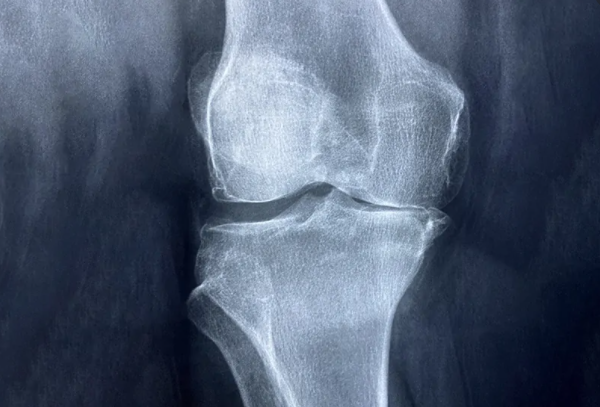

연골은 움직일 때 관절과뼈를 보호하는 쿠션입니다. 그러나 나이가 드신 분들이나 골관절염 환자의 경우에는 연골이 시간이 지남에 따라 마모되어 통증과 불편함을 유발할 수 있습니다.

골관절염은 노년기와 관련이 없는 경우가 많지만 연골은 모든 사람이 다양한 속도로 퇴화됩니다. 따라서 연령이나 상태에 관계없이 연골을 보호, 유지, 보충 및 복구할 수 있는 영양가 있는 음식을 섭취하는 것은 권장합니다.

연골 보호

연골 마모는 자연적으로 발생하며 완전히 멈출 수 없다는 사실을 알아야 합니다. 그러나 건강한 생활 방식을 유지하면 연골 회복을 촉진할 가능성이 높아집니다.